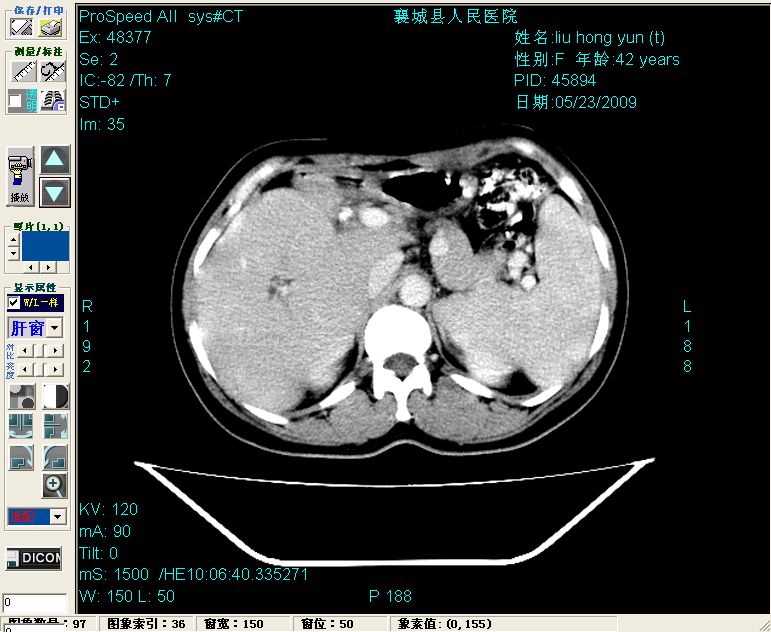

平扫:

平扫左肝外叶体积显著减小,左肝外叶见多房囊性低密度区,左肝实质及右肝前叶浅表实质呈低密度改变,左肝及右肝前叶胆管扩张,脾大

增强动脉期前述低密度区轻度早其强化,门脉期强化程度显著增高,延期扫描强化程度下降,但仍为相对高密度影

胰头部见结节状高密度影,其前方略可分辨扩强胆部管,平扫到增强始终有,但现在尚难与胃肠造影剂鉴别.

结合病史考虑,1现在引起黄疸体征的原因应该是胆总管胰段结石阻塞,建议局部胃肠造影剂排空后复查.

2左肝及右肝前叶表现考虑胆囊摘除术后所致的肝动门脉瘘形成,慢性纤维组织炎性增生.不完全除外左肝胆管细胞癌

3脾大,可能与动门脉瘘所致门脉高压有关